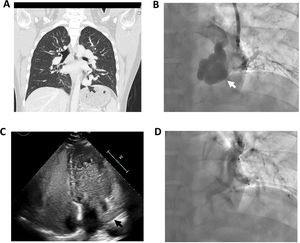

Imaging of the pulmonary arteriovenous malformation. An initial thoracic CT revealed (A) dilated and tortuous pulmonary arteries and veins that joined together in a nodule of 32mm in the left lower lung lobe consistent with a pulmonary arteriovenous malformation (gray arrow); this was also confirmed during pulmonary angiography (white arrow, B). A transthoracic contrast echocardiography with agitated saline was performed. After ten cardiac cycles, countless saline bubbles were observed traveling through the left inferior pulmonary vein (black arrow) into the left atrium (C) without a Valsalva maneuver suggestive of significant right-to-left shunt. It also showed dilated right ventricle, systolic flattening of the interventricular septum and increased tricuspid regurgitation velocity. The pulmonary arteriovenous malformation was treated via vascular plug closure (D).

A 35-year-old male with a history of hypothyroidism presented with exertional dyspnea, but no hemoptysis or spontaneous epistaxis. His oxygen saturation was 95%. A thoracic CT revealed a PAVM in the left lung (Fig. 1A). Transthoracic echocardiography showed agitated saline bubbles draining into the left atrium via the pulmonary vein suggestive of significant right-to-left shut (Fig. 1C) and signs of pulmonary hypertension (PH). Right heart catheterization confirmed severe pre-capillary PH with a pulmonary arterial wedge pressure of 8mmHg, mean PA pressure (mPAP) of 63mmHg, pulmonary vascular resistance (PVR) of 14.9WU and cardiac output of 3.7L/min. Abdominal imaging showed normal liver vasculature. We cannot rule out hereditary hemorrhagic telangiectasia (HHT), though the patient only met one Curaςao criterion [1]. Genetic testing identified a heterozygous variant (ACMG class 3) in the growth differentiation factor 2 (GDF2) gene (c.958A>G(p.Ser320cys)). The patient was treated with tadalafil and ambrisentan. He exhibited marked symptomatic and hemodynamic improvement (mPAP:44mmHg, PVR: 4.5WU, cardiac output: 7.5L/min). He then successfully underwent endovascular plug closure of the PAVM.